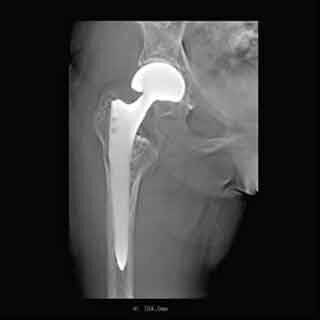

島津製作所は6月17日、同社X線TVシステム「SONIALVISION G4」向けに、金属アーチファクトを大幅に低減できる独自のトモシンセシスアプリケーション「T-smart」の販売を同日より開始すると発表した。

同製品は金属分離と逐次近似法を併用したトモシンセシス画像再構成方法を採用しており、従来法と比較して金属アーチファクトを大幅に低減することができる。金属の影響を受けずに骨の状態を把握できるため、人工関節置換術後の評価や骨折部の金属固定状態の経過観察に効果を発揮するとしている。